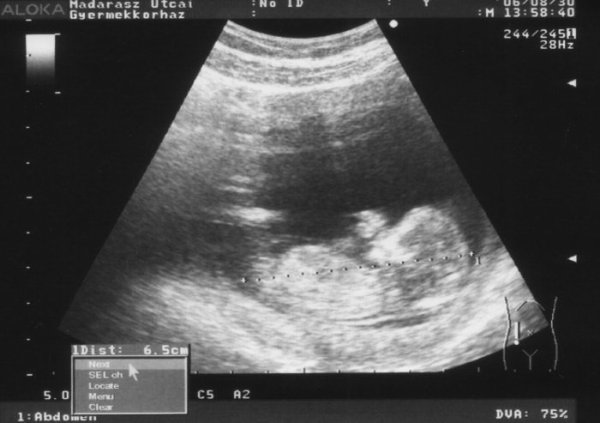

De a képeket még felrakom, mert én most "a boldogságtól ordítani tudnék..." Voltunk ma uh-n a férjemmel, és láttuk a babánkat mozogni is, cumizta az ujját, utánna két kézzel fogta a fejét(gondolom akkorra már eleg volt az uh-ból :oops: )

A képen jól látszik a bal keze, éppen cumizza :lol:

Ja, és már 6.5 cm!!! 2 hét alatt dupplájára nőtt!!! Pénteken megint uh, az már a hivatalos lesz, akkor néznek tarkóredőt!